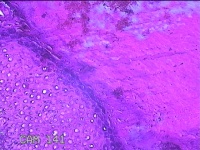

左足部包块

性别

女

年龄

34岁

临床诊断

皮下囊肿

一般病史

发现左足部包块4年余,无明显疼痛及不适。

标本名称

大体所见

灰白暗红色组织1.8x1.1x0.8cm一块,表面带梭形皮肤1.8x0.8cm,皮下见包块1。8x0.8x0.7cm一个,切开包块呈实性,切面灰白粉红色,质软。

图1